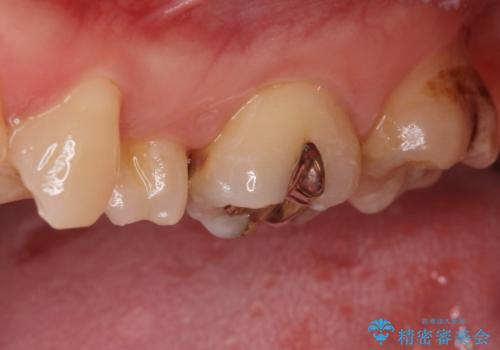

- 奥歯の歯が黒いとの事で来院された患者様です。

頬側の歯の面も粗造になっていたので、インレーではなくジルコニアクラウンでの治療となりました。